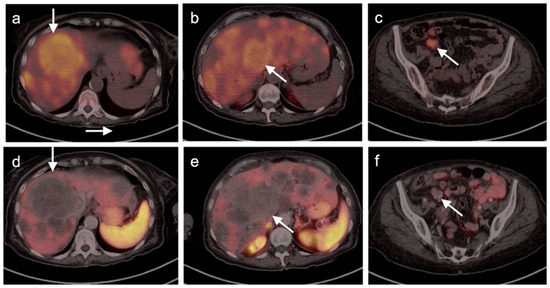

- Gao, Y.-J.; Yang, Z.; Yu, J.-Y.; Li, N.; Wang, X.-J.; Zhou, N.-N. Potential application value of PET/computed tomography in retroperitoneal leiomyosarcoma and a literature review. Nucl. Med. Commun. 2021, 42, 800–810. [Google Scholar] [CrossRef]

- Subramaniam, S.; Callahan, J.; Bressel, M.; Hofman, M.S.; Mitchell, C.; Hendry, S.; Vissers, F.L.; Van der Hiel, B.; Patel, D.; Van Houdt, W.J.; et al. The role of 18 F-FDG PET/CT in retroperitoneal sarcomas—A multicenter retrospective study. J. Surg. Oncol. 2021, 123, 1081–1087. [Google Scholar] [CrossRef]